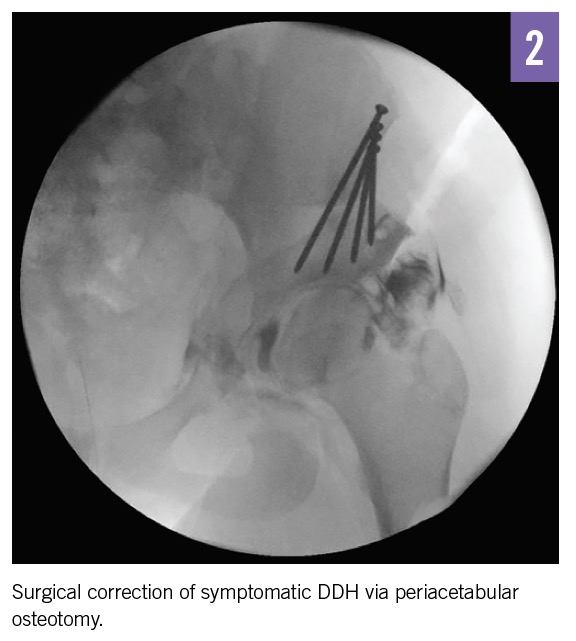

Dysplasia diagnosed in adolescence or early adulthood is corrected with surgery.1 Most patients achieve radiologic improvement and improved Harris hip scores, a 10-item scoring system that includes pain, function, absence of deformity, and range of motion. The complications of surgery—avascular necrosis (2% to 3%), loss of fixation (1% to 6%), and pelvic nonunion (4%)—while rare must be balanced with the benefits of improved function and delay in joint degeneration.1,13,14

Outcome of the case. After the risks of nonsurgical management were discussed, our patient, her family, and her surgeon agreed on surgical correction with a periacetabular osteotomy (Figure 2). The patient asked when she could return to playing soccer and was told that return to play was reported in 80% of female patients at a median of 9 months after surgery.15